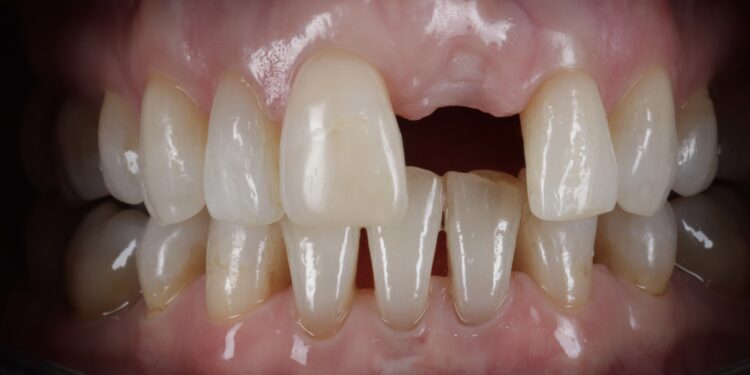

This patient presented with orthodontic crowding and a dislike for her enlarged crown on UL1 and “higher gum line.” She requested teeth straightening and an improvement in the gum line on this crown.

Once the orthodontic treatment was completed, the site was re-evaluated, and it was clear to see that the gingival zenith had significantly improved. The patient was advised that without re-contouring the mesial aspect of the contralateral central incisor there would be a midline black triangle. She rejected the option of composite addition to alter the triangular shape of the UR1 and thus we proceeded to complete the treatment without this. The implant was placed with simultaneous buccal GBR & connective tissue graft following a transmucosal approach. Following a healing period of 4 months, the restorative treatment was initiated with a temporary crown to develop the emergence profile. Once the gingival zeniths had been matched, the patient was delivered a permanent screw retained crown.